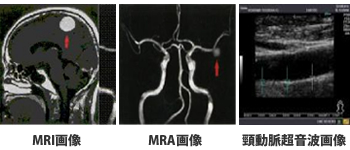

中外医学社 | 書籍詳細。臨床心臓CT学-基礎と実践マネージメント | 小山 靖史, 鈴木 諭。アプリケーション(心臓領域) | REVORAS。【N☆】令和6年(新米)コシヒカリ1等米10キロ。CT検査 | 戸畑共立病院。オプション検査 | 人間ドック健診センター | 大田区蒲田 牧田。。桜橋渡辺未来医療病院 MDCT検査予約。医学出版_循環器ナーシング16年6月号。CT検査 | 戸畑共立病院。心臓特化型画像診断センター「心臓画像クリニック(CVIC)飯田橋。朝倉書店『内科学』(第12版)デジタル付録。メジカルビュー社|診療放射線技師|心臓CT活用マニュアル。心臓Ⅰ:Step and shoot technique 岩城 卓(横浜栄共済病院。「臨床心臓CT学 基礎と実践マネージメント」小山 靖史定価: 22000円 (20000円+税)ぼぼ未使用でパラパラと見ただけで、状態はよいと思われます。書き込みも見返しましたがありませんでした(万が一あったら申し訳ございません)。表面に多少のスレやキズはあります。また天面に名前の印鑑がありマジックで消しています。あくまで写真のものをお渡しということでよろしくお願い致します。ご質問や価格交渉ありましたらメッセージくださいm(._.)m循環器内科、内科、カテ、カテーテル、CAG、PCI、FFRインターベンション、読影、放射線冠動脈、動脈硬化冠動脈疾患、虚血性心疾患、狭心症、心筋梗塞高血圧、糖尿病、脂質異常症、肥満